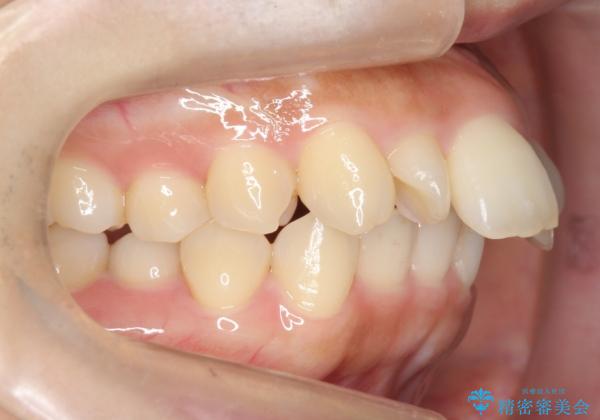

上下のかみ合わせが1本分左右ともずれていました。

下顎がとても小さく後方位であるため、オトガイの閉口時のシワは完全になくすことは難しかったですが、前歯も大きく下がり満足していただきました。

矯正治療は審美的な側面を持っておりますが、小さすぎる下の顎に口元を無理やりあわせるのも、歯の移動量が大きすぎて適切な治療とは言えないと思います。健康を損なう美容整形とは違うからです。前歯については、適度に下げる量をコントロールすることも大事です。